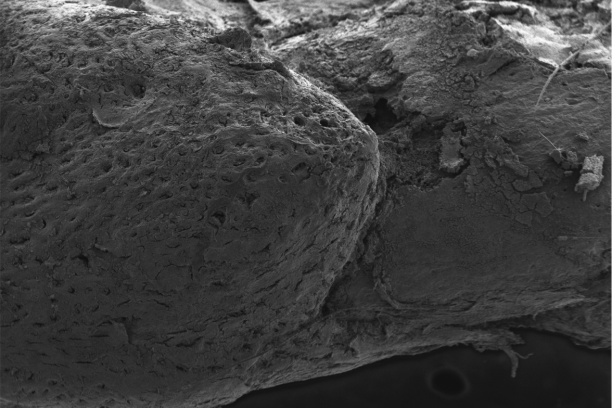

The Cassat Lab studies host-pathogen interactions during invasive bacterial infection, with a special emphasis on understanding how infection and inflammation perturb musculoskeletal cell biology. Osteomyelitis (bone infection) is one of the most common invasive bacterial infections in children, and it also occurs frequently in adults after trauma or surgery. The bacterial factors that promote survival in the bone, as well as the host factors that protect from osteomyelitis, are poorly defined. We have developed a variety of tools to understand how bacteria and inflammation trigger changes in bone biology, including a murine model of Staphylococcus aureus osteomyelitis, high-resolution 3D imaging of bone remodeling, and cell culture models of osteoblast and osteoclast proliferation and function.